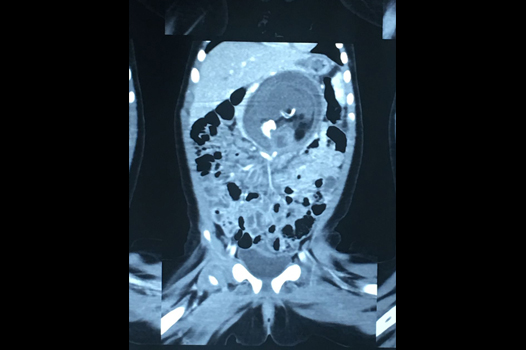

Foetus-In-Fetu (3)